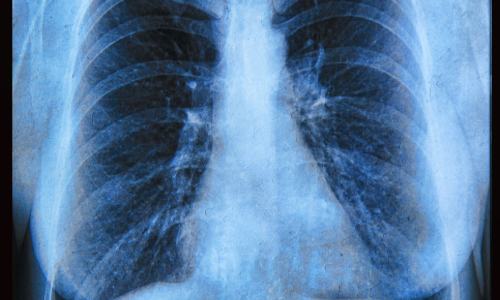

Hello, I am Joshua Robertson, a medical student starting at the Keck School of Medicine of the University of Southern California, USA. I initiated writing this review when I was an undergraduate researcher in the Goldberg Lab at the Emory University School of Medicine Atlanta, Georgia, USA. The Goldberg Lab studies bacteria and how they participate in infections, focusing on the respiratory infections associated with cystic fibrosis (CF). CF is a genetic disorder that causes impaired water balance in epithelial cells, which creates a mucosal environment susceptible to chronic microbial infections associated with morbidity and mortality.

CFTR modulator therapies return function to essential ion channels and bring back water balance. The combination therapy of Elexacaftor, Tezacaftor, and Ivacaftor (ETI) was approved in the US in 2019 and Europe in 2020. ETI therapy, known as Trikafta and Kaftrio commercially, has transformed the lives of pwCF. These therapies have led to improved lung function, increased life expectancy, and a reduction in chronic infection symptoms. Microbiologists like my colleagues in the Goldberg Lab have a particular interest in how these changes impact pathogens. The antibiotic resistance crisis had already displayed how positive innovations can have severe unintended consequences, especially in the dynamic, evolving world of microbes. For these reasons, I was encouraged to write a review about this topic for which the scope quickly expanded to the entire pulmonary microbiota.

We uncovered a lot of interesting findings in writing this article. There is a lot that we do not know about ETI therapy and its relationship with the CF lung, but many of the studies were able to provide some insight into particular areas, which creates a clearer overall picture. One consistent finding was that the most dangerous CF pathogens including P. aeruginosa remain present in the CF lung even if their prevalence has decreased. Along with the evolution and genetic changes identified in the bacterial populations, there is a lot to be done regarding the future trajectory of the pathogens in the CF lung.